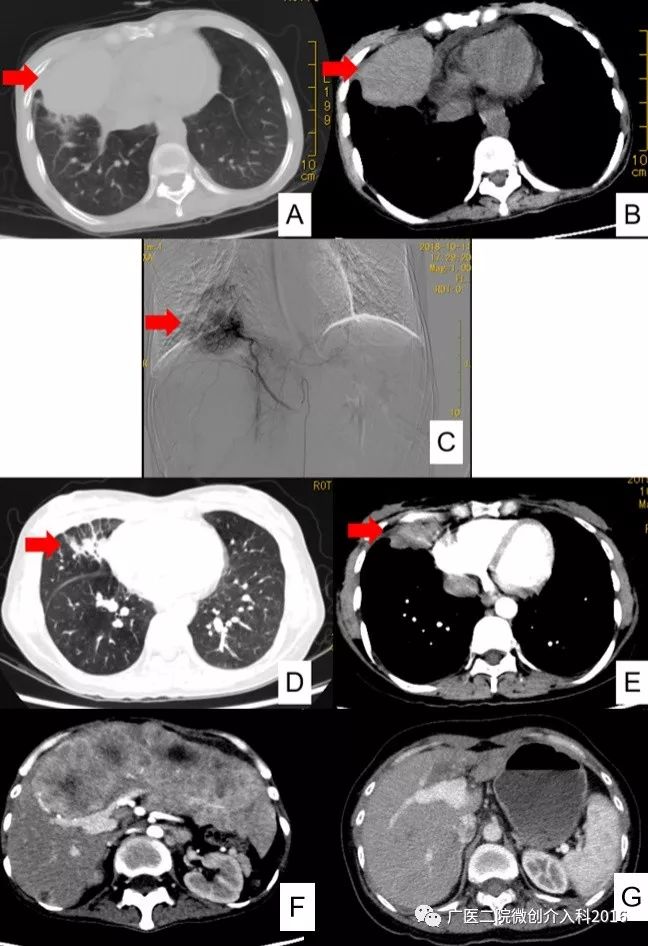

女性,42岁,肺癌晚期(图A、B),病理:低分化鳞状细胞癌。该患者在外院做过多次静脉化疗无效,后到我科就诊,入院时患者一般情况非常差,恶病质、卧床,体重42kg。入院后基因检测提示:无基因突变、无靶向药可用,TMB 72个突变/Mb,MSI-H。我科为其制定的治疗方案:动脉灌注化疗(图C)联合PD-1免疫治疗。经过2次动脉内灌注联合免疫治疗后3个月,患者步行入院复查,体重明显增加4kg,肺内肿瘤和肝转移灶明显缩小。后又单一进行3次免疫治疗,10个月复查肺内肿瘤、肝内转移基本消失(图D-G)。

专家点评

该患者为晚期肺癌患者并肝转移,全身静脉化疗无效。基因检测提示无靶向药物可用,但其TMB值高、MSI-H。MSI-H、TMB是预测免疫治疗疗效的重要指标之一,我科采用局部动脉灌注化疗联合PD-1免疫治疗,达到了非常好的疗效,介入治疗联合免疫治疗为晚期肺癌患者带来了新希望!